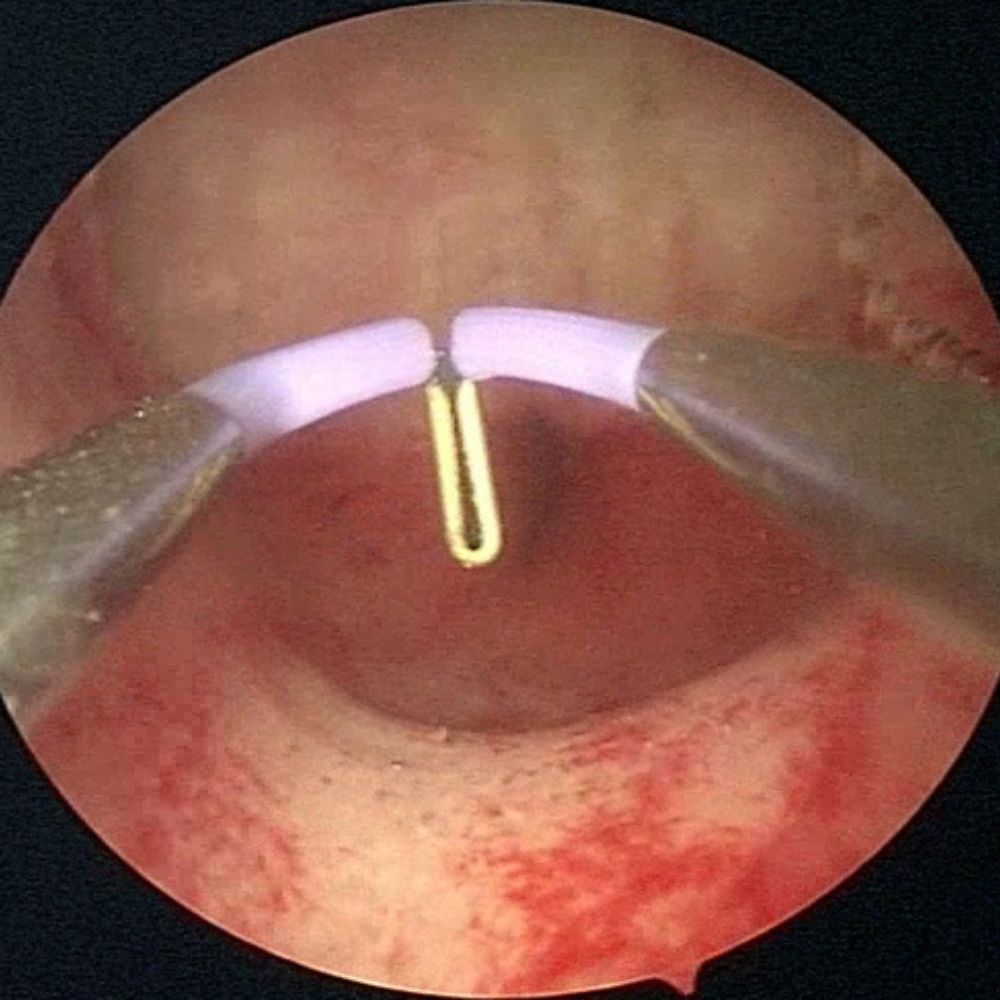

Notre toute dernière génération de lentilles, conçues pour tirer pleinement profit de la HD, procure des images riches, parfaitement résolues, même en périphérie. Cette hyper-résolution, couplée à une lumière répartie de manière véritablement homogène, est gage d’une très grande profondeur de champ.

Vous serez «net partout» ! Notre hystéroscope HD est bien entendu autoclavable. Sa conception sous forme de trois tubes distincts le rend résistant, durable mais aussi aisément réparable en cas d’accident.